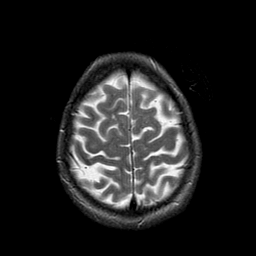

Metastatic Adenocarcinoma of the Colon: T2-weighted MR -- Slice #20

[Home][Help][Clinical] Slice 20